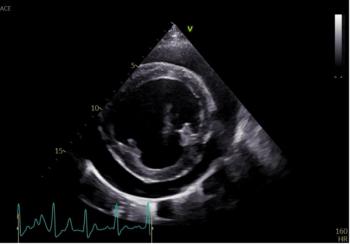

The transcatheter edge-to-edge repair procedure is a minimally invasive treatment for mitral regurgitation.

Gianluca Bini, DVM, MRCVS, DACVAA, explains what the most common heart diseases are for canine and feline patients

So you heard a heart murmur during a physical exam, now what?